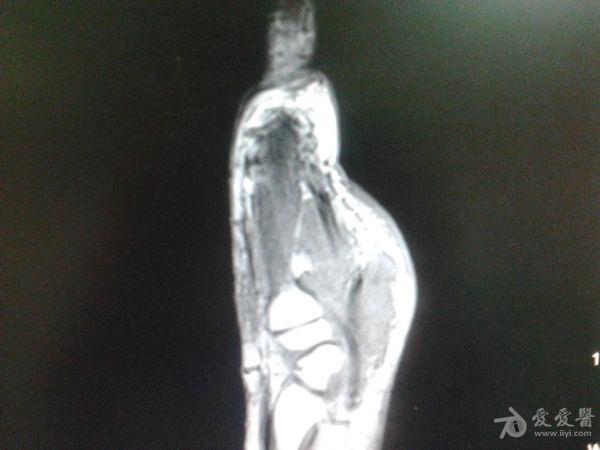

右第一掌骨、大多角骨肿瘤

男性患者,81岁,右手肿痛3个多月。无任何其它症状。体查:右手第一掌骨部肿胀明显,第一指活动受限,余四指活动可,腕关节活动小部分受限,活动时会痛。影像学检查如下。活检示:弥漫性大B细胞淋巴瘤。大家看看需不需要截肢?现在有人主张手术;有人主张不手术,直接化疗。大家有什么看法?

从以上资料看已经影响到腕关节了,还是截吧,不能姑息